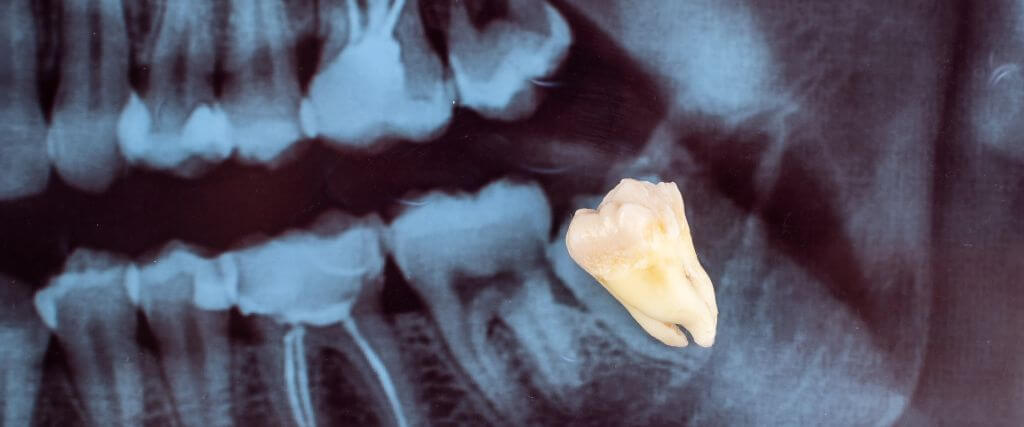

If you need to have your wisdom teeth removed, your dentist or oral surgeon will begin with a comprehensive examination. They will also take X-rays to assess tooth position, root structure, and proximity to nerves and sinuses.

Your procedure’s complexity depends on several factors, including tooth position, root development, and impaction level. Extracting fully erupted teeth is simple and requires only basic instruments. However, impacted or partially erupted teeth often require more complex surgical extraction.

During the extraction, your dentist or surgeon creates small incisions in the gum tissue, widens the socket, removes bone (when necessary), and carefully extracts the tooth. Large teeth may be sectioned into smaller pieces for easier removal. The surgeon cleans the extraction site, places stitches if needed, and positions gauze to control bleeding.